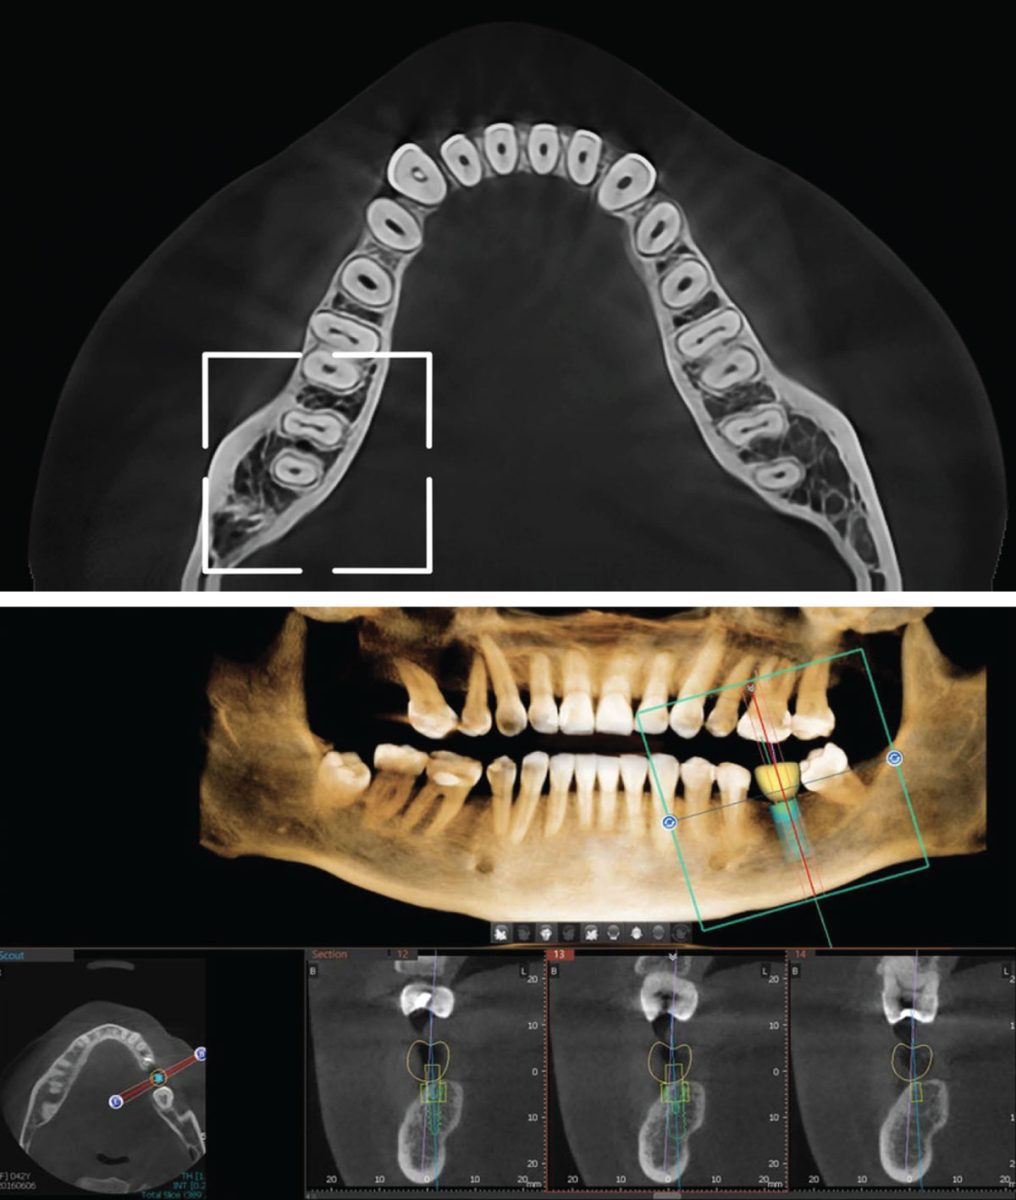

CBCT Semi je precizan 3D snimak jedne vilice (gornje ili donje), namenjen ciljanoj dijagnostici uz nižu dozu zračenja i brzu akviziciju snimka. Ova vrsta snimanja idealna je kada klinička indikacija zahteva detaljan prikaz ograničene regije, bez potrebe za snimanjem obe vilice.

- Planiranje ugradnje implantata u jednoj vilici

- Procena odnosa zuba sa anatomskim strukturama (sinus, mandibularni kanal)

- Visoka 3D rezolucija i izuzetna dijagnostička preciznost

- Multiplanar i 3D rekonstrukcija za kompletnu analizu